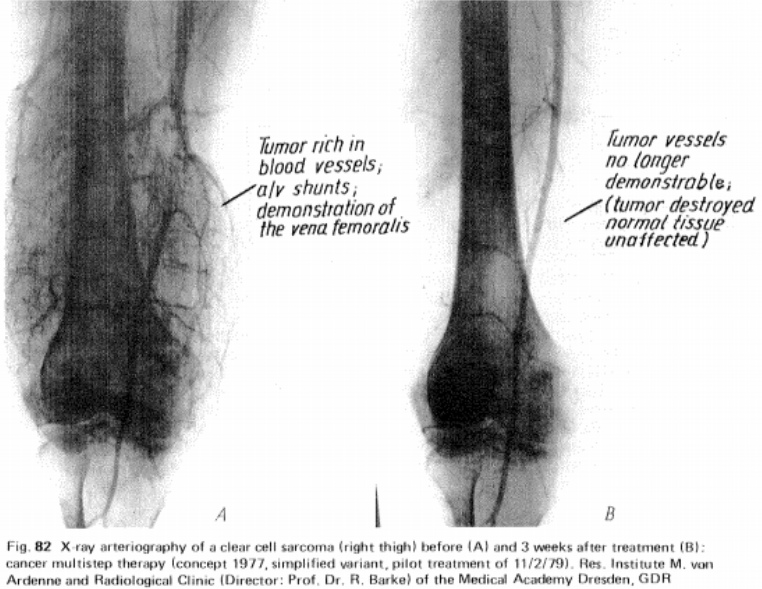

If you are a health care practitioner or researcher, you might be inclined to investigate what Manfred von Ardenne's textbook methodologies might be able to do in a clinical environment that go beyond the sports and life performance aspects we've discussed. Click the image for context.

To expand on this idea in a parallel direction, read the study abstract.